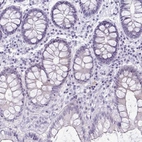

Immunohistochemistry analysis in human skeletal muscle and colon tissues using Anti-RYR1 antibody. Corresponding RYR1 RNA-seq data are presented for the same tissues.